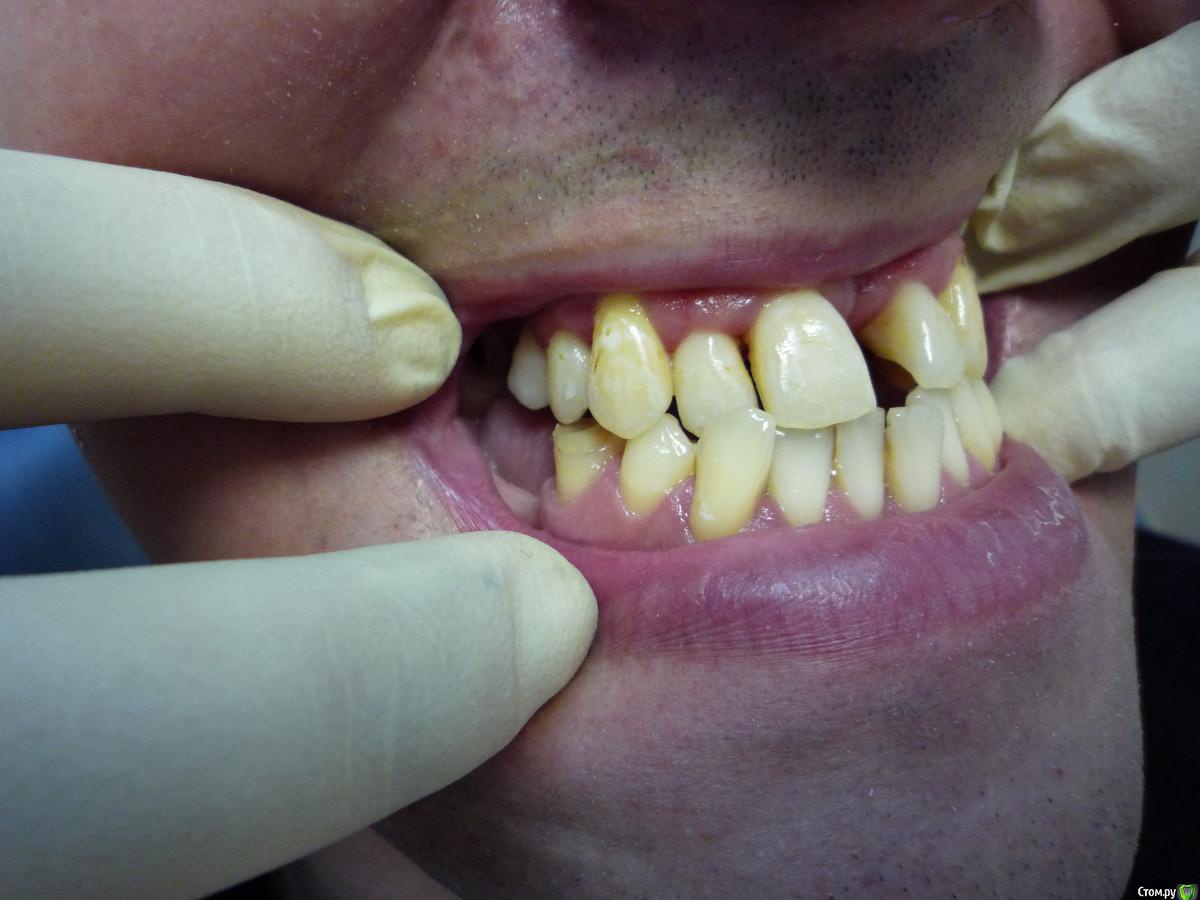

Jeniaspb Опубликовано 20 июля, 2015 Поделиться Опубликовано 20 июля, 2015 Пациент 32 года. Фото к сожалению только те, что есть. По ТРГ верхняя микрогн и нижняя прогнатия, протруз резцов в/ч 132^ и ретрузия резцов н/ч 68^, а так же переднее положение головки н/ч. Идеально сделать гнатич хирургию, но пациент идет в полный отказ, в связи с чем имеются следующие мысли:1) провести ТЭНС терапию с определением положения н/ч, в надежде на то, что она сместится хоть чуточку назад.2) если н/ч сместится каппа на н/ч с последующ окклюз накладками3) б/с на нижн зубн ряд и попыткой смещения дистально премоляров для освобожд места резцам4) б/с на в/ч и попытки камуфляжа этого всего...5) имплантация и затем протезирование.Вопрос самый главный:на сколько велики мои шансы сделать обратное перекрытие, которое я не смогу вернуть?) Ссылка на комментарий

Yana guapa Опубликовано 22 июля, 2015 Поделиться Опубликовано 22 июля, 2015 Есть подозрения на нарушения внчс, н/ч имеет норм размеры, опять таки есть подозрения, что н/ч занимает не центральное положение! только подозрение?)) при таком положении НЧ , при таких дефектах зубных рядов дисфункция обязана быть)) Каким образом: расслабление мышц приведет н/ч в ее центр положение. Что: изменение положения н/ч за счет см вышеДля чего: перемещ н/ч назад в идеале! какой смысл проводить сейчас "расслабление" если НЧ физически не сможет сместиться назад при обратном перекрытии 1.2 зуба (это же блок). или Вы хотите сделать немалое разобщение , увеличив ротацию НЧ, и о каком расслаблении тогда речь? мне не понятно. (имхо) Ссылка на комментарий